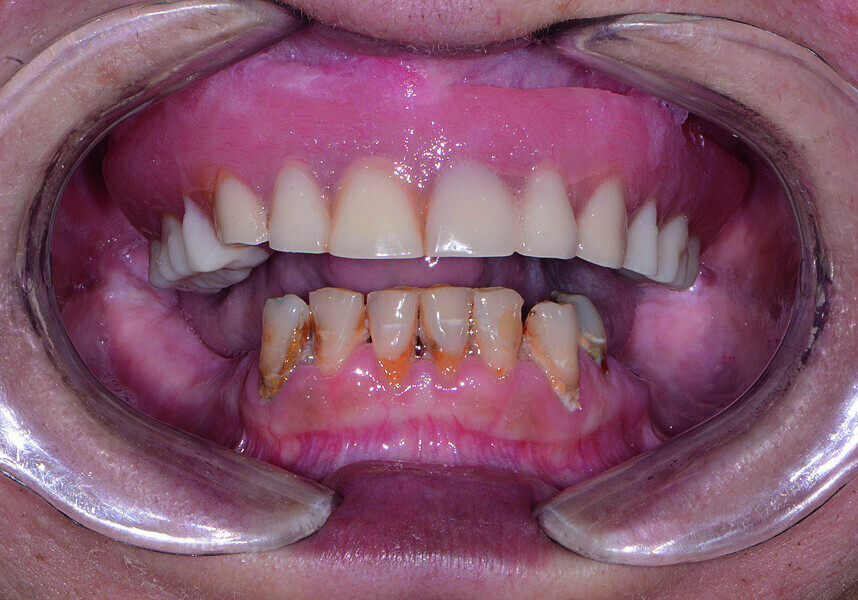

Fig. 1: Pre-op retracted view.